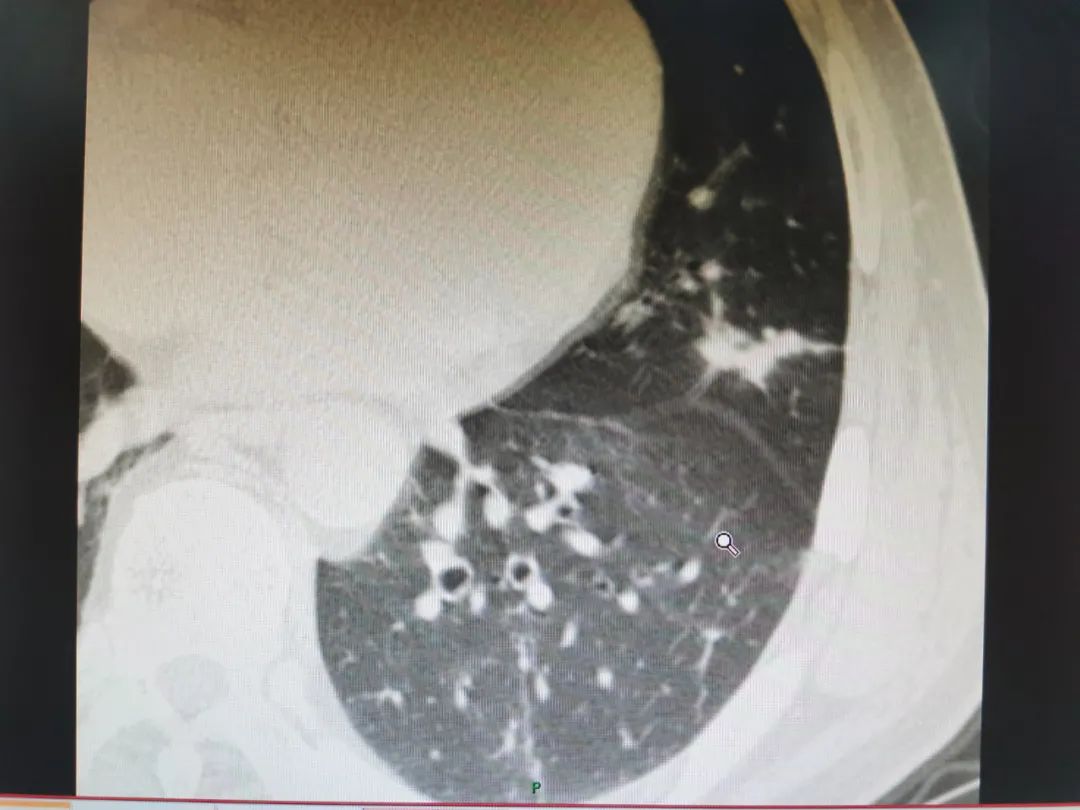

你覺得不能着急,你補做了胸部靶CT,因為靶CT看的更加清楚,相當於拿了放大鏡看結節,你用MPR做了重建,發現結節確實形態不好。

靶CT左上肺病灶